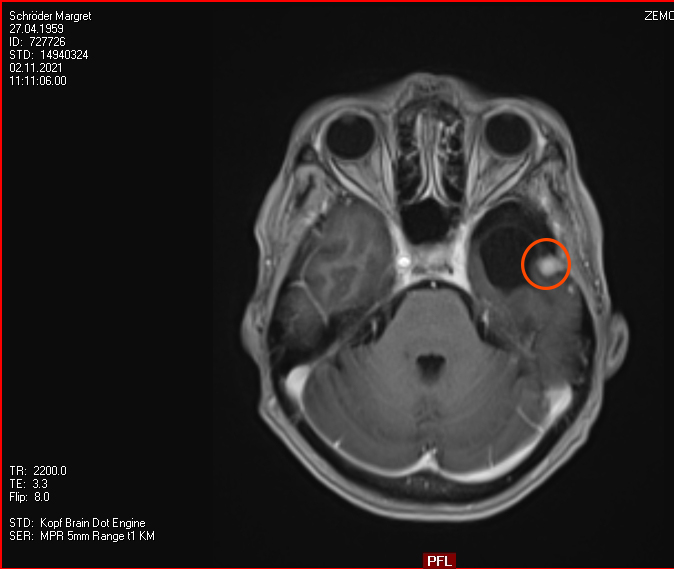

Januar 2021: Ein Kampf gegen Erbsen im Kopf mit modernen Mitteln

Also habe ich mich entschieden, dem Rezidiv nicht mehr länger beim Wachsen zuzusehen und habe Kontakt aufgenommen zur Strahlenmedizin in Hamburg, iCERA – Spezialisten für Radiochirurgie – „Präzisionsstrahlenbehandlung - geschnitten wird dabei nicht“. Das ging alles ziemlich schnell, im Dezember die Bilder auf CD nach Hamburg geschickt, ein Telefongespräch mit dem Professor, der zu einer Vorstellung bei ihm geraten hat, ein Vorgespräch im Januar und nun ist es am 26.01.2021 schon passiert – das Gammknife hat aus fast 200 Strahlenquellen für ca. 20 Minuten aus verschiedenen Richtungen auf den Tumor „geschossen“, so dass am Tumorpunkt die Strahlen zusammenfanden und so gemeinsam in diesen paar mm³ genug Energie entstand, um einen Schaden an den Zellen anzurichten ohne das gesamte Gehirn zu schädigen. Große Medizintechnik der Neuzeit. Meine Krankenkasse zahlt, was erstaunlicher Weise nicht für alle Kassen gilt.

Nun muss man warten, dass der Körper auf richtige Weise auf die Behandlung reagiert und das Wachstum des Tumors gestoppt worden ist. Das wird man erst Ende April sehen, wenn ich zum nächsten MRT nach Hamburg fahren werde. Aber weiter gilt, mir geht es gut, nix tut weh und all meine kleinen Tests zur Funktion des Gehirns (schweres Sudoku, Einkaufen mit dem Rad und bei schlechtem Wetter (Nieselregen/Schnee auf der Brille) und diese Webseite fix erweitert) haben geklappt, mehr will ich nicht!

April 2021:Leider keine Veränderungen

Am 29.4.2021 war ich zum Kontroll-MRT drei Monate nach der hochmodernen Strahlentherapie, dem Gamma-Knife. Leider ist das Ergebnis: den Tumor hat diese Behandlung nicht beeindruckt, keine Änderungen zu erkennen. Der Arzt schlägt eine weitere Kontrolle in 6 Monaten vor. Ich finde es etwas schwer, dieses Ergebnis einzuordnen. Aber so ist es nunmal. Vielleicht ist es ja normal, und wird erst später gut (siehe Punkt 4).

2. November 2021: Leider etwas gewachsen

Heute war ich im MRT im Bremen. Der Befund des auswertenden Arztes ist, dass er der Meinung ist, dass der Tumor etwas gewachsen ist. Ich habe mir die Bilder angesehen und versucht diese Aussage zu verstehen. Vermutlich ist sie richtig, aber das Wachstum ist nicht heftig nur vielleicht von 0,7 cm auf 0,8 cm. Aber Gamma-Knife hat es offensichtlich nicht entfernt.

Heute war der Termin beim Chirurgen, leider schon um 9:00 Uhr und natürlich wollte ich die knapp 20 km mit dem Rad zurück legen, Stephan wollte gerne mitkommen. Leider war die bereits abgegebenen CD nicht eingelesen worden und so musste erstmal die Datenverarbeitung arbeiten und wir warten, bis wir eine Auskunft bekommen konnten. Fazit: Der bestehende Tumor ist kaum gewachsen. Aber es hat sich leider ein 2. Fund ergeben, sehr klein aber deutlich sichtbar. Aber Maßnahmen sind erstmal nicht notwendig.